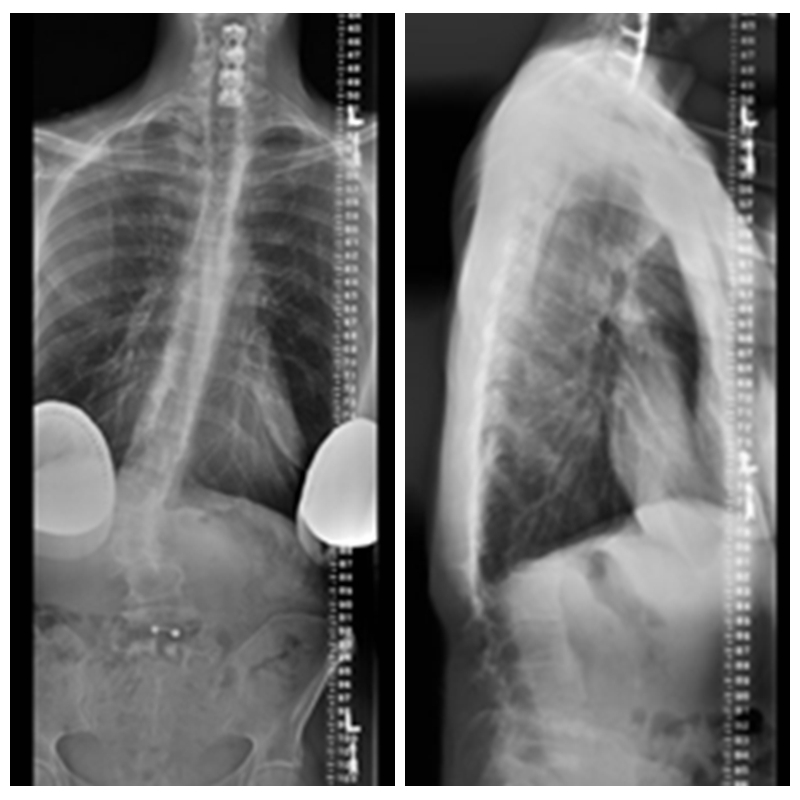

51岁,女性,腰椎术前矢状位明显失平衡,术后多年加重;

期望解决下肢痛及站立问题。

诊断:腰椎局部融合术后,临近节段后凸畸形。

术前X线

予患者行后路PSO截骨,T10-骨盆固定。

术后X线